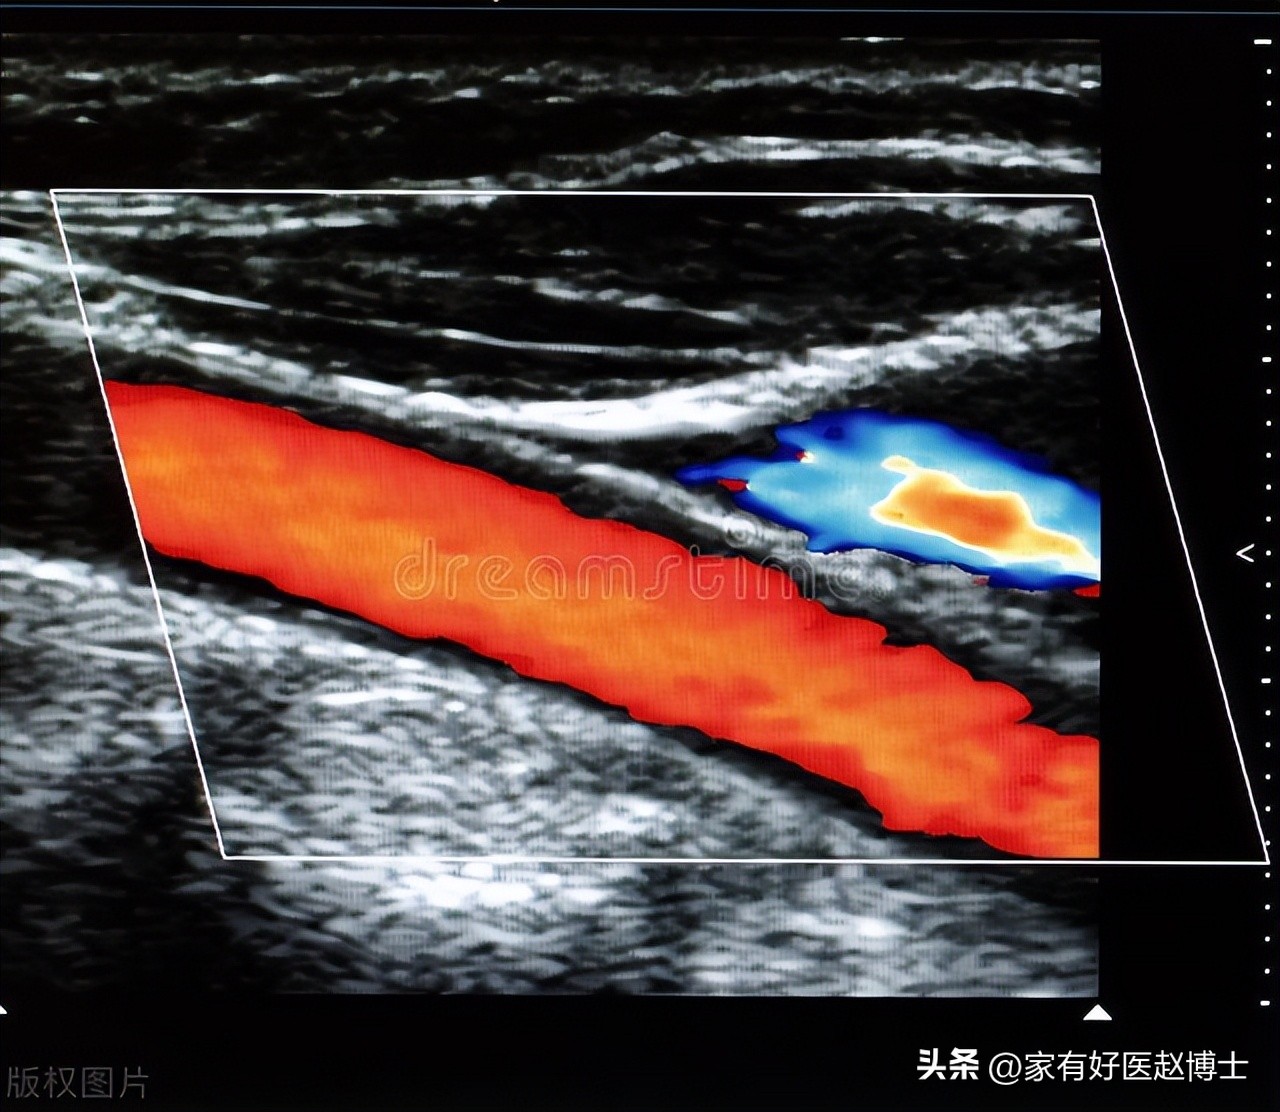

一 有没有引起“狭窄”?

2022版《动脉粥样硬化斑块的筛查与临床管理专家共识》明确指出:只要颈动脉斑块引起了颈动脉狭窄≥50%,那么,这种斑块就可以直接归类于“极高危”这个级别,属于危险程度最高的斑块。

原则上,这种对治疗决策有很大影响的情况,往往是超声报告里的“重中之重”。只要超声医生发现了斑块有引起血管狭窄的迹象,那么,就一定会在检查报告当中对此进行描述。

因此,假如您的超声报告里没有特别提到“斑块引起颈动脉狭窄”,那么,就往往意味着暂时还没有出现这种情况。